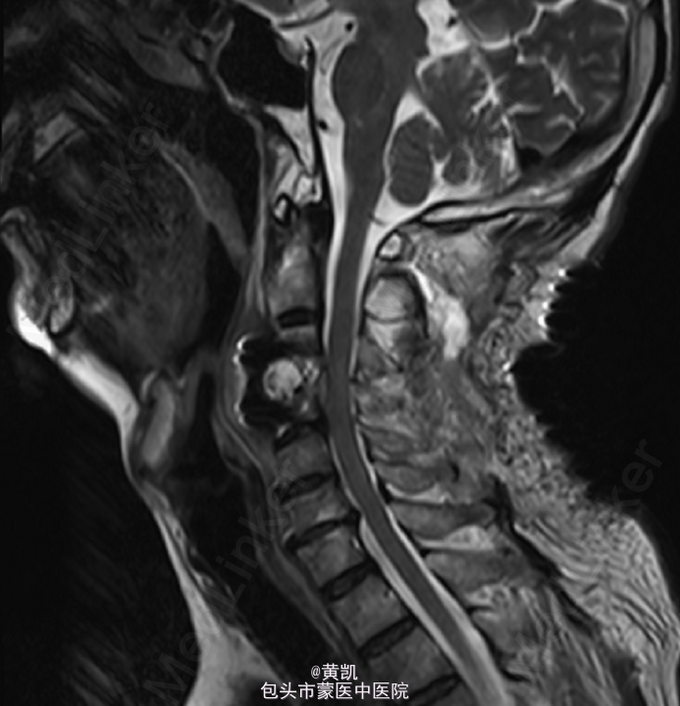

患者,男,63岁,因“ 颈部疼痛2月,加重伴双手无力15天”入院。

脊柱无明显畸形,颈椎压痛明显,双侧上肢远端肌力II级,近端肌力III,肌张力明显减低。左下肢肌力III级,右下肢肌力II级,肌张力明显减低,双侧Hoffman征阴性,巴氏征阴性,病理征阴性。MRI 2015-04-15:C3/4结核伴椎旁脓肿形成。 T8,T9,T10,T11,T12椎体结核伴椎旁脓肿形成。